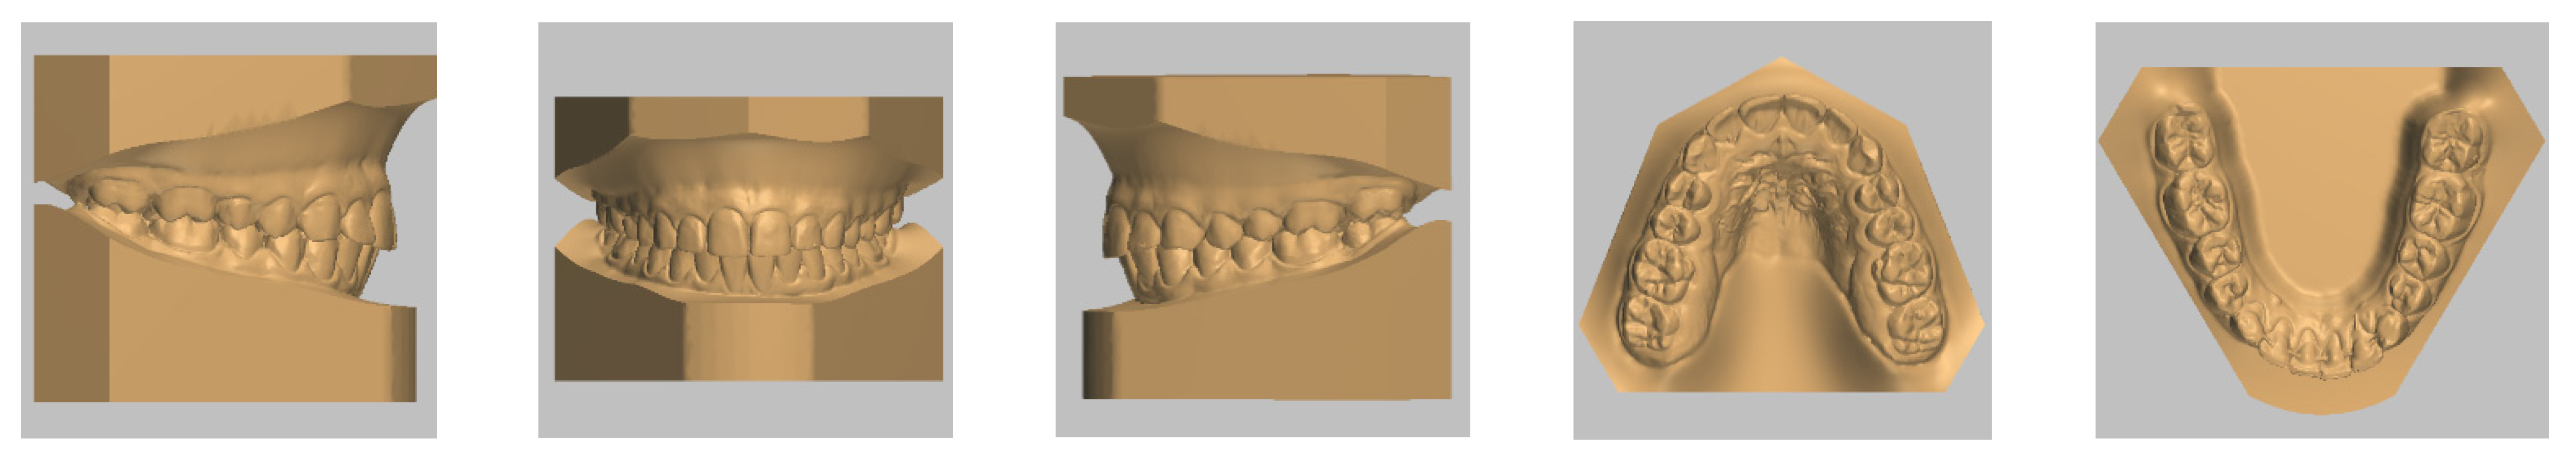

4. Case Report

4.3. Treatment Strategy

4.4. Treatment Progress